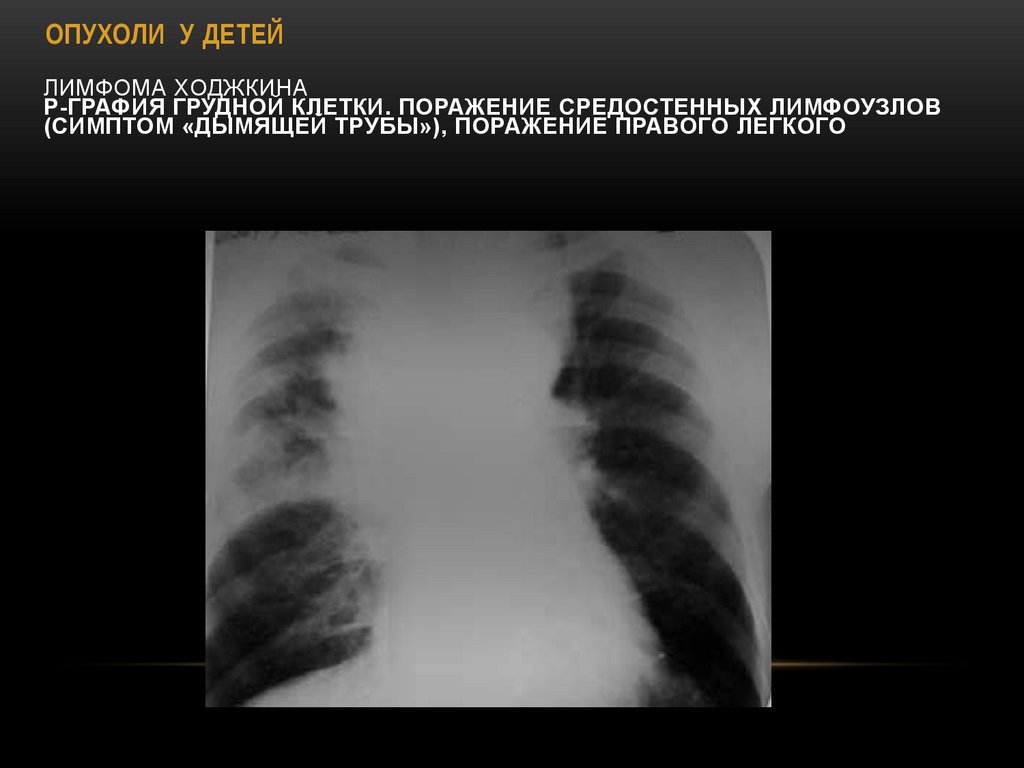

45. Лимфома Ходжкина Р-графия грудной клетки. Поражение средостенных лимфоузлов (симптом «дымящей трубы»), поражение правого

ОПУХОЛИ У ДЕТЕЙ

ЛИМФОМА ХОДЖКИНА

Р-ГРАФИЯ ГРУДНОЙ КЛЕТКИ. ПОРАЖЕНИЕ СРЕДОСТЕННЫХ ЛИМФОУЗЛОВ

(СИМПТОМ «ДЫМЯЩЕЙ ТРУБЫ»), ПОРАЖЕНИЕ ПРАВОГО ЛЕГКОГО